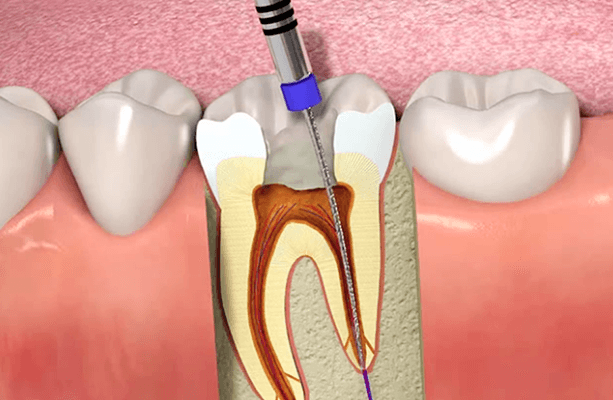

Root Canal Treatment

Root canal therapy treats infected tooth pulp and saves natural teeth. It involves cleaning, disinfecting, and sealing the canals. Prevents extraction and relieves pain. Done under local anesthesia with minimal discomfort. Helps maintain long-term oral health.